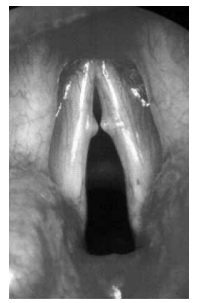

Qual alteração está comumente relacionada à lesão apresentada na laringoscopia a seguir?

Provas